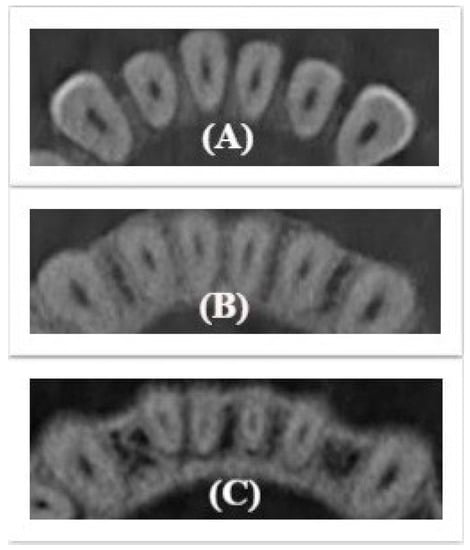

For maxillary anterior teeth: the cross-sectional root canal shape was defined to be round for incisors and oval for canines in the three thirds in each age group. No statistical differences were observed for this group of teeth (Figure 1). The significant difference was observed in the diameter of the root canal in elderly group which was observed to be smaller than other age groups (P < 0.05).

Figure 1.

Unchanged cross-sectional root canal shape for maxillary anterior teeth (A) Coronal; (B) Middle; (C) Apical.